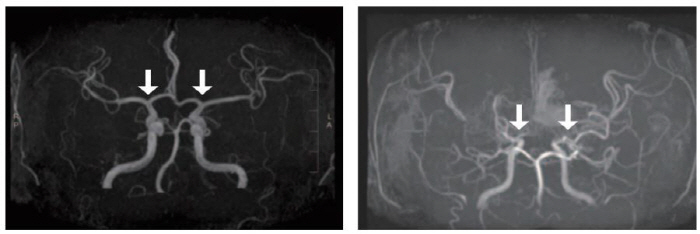

Childhood moyamoya disease is a chronic progressive cerebrovascular disease in which the blood vessels that supply blood to the brain gradually narrow without any specific cause. The condition creates abnormal microvessels to make up for insufficient blood flow, which are difficult to supply enough blood flow and are prone to rupture, which can cause childhood strokes such as cerebral infarction and cerebral hemorrhage.

The confirmation of Moyamoya disease is made through cerebrovascular angiography. However, as sedation or anesthesia were often required before testing, a new diagnostic method was needed due to the high burden on pediatric patients. Recently, cerebrospinal fluid has attracted attention as a useful resource for discovering biomarkers for central nervous system diseases, but large-scale research on moyamoya disease using it was insufficient.